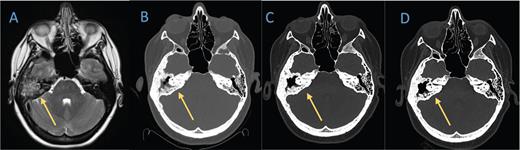

Axial T2 sequence of A) a brain MRI from 2019 demonstrates diffuse opacification of right mastoid air cells and lytic changes of the right temporal bone. A B) head computed tomography (CT) scan obtained in February 2021 shows erosion of the bony septate and partial opacification of the mastoid air cells. C) Nine months later, CT of the head reveals an interval decrease in the amount of fluid collection in the mastoid portion of temporal bone and reactive sclerotic changes. D) The most recent head CT in July 2022 shows stable changes.